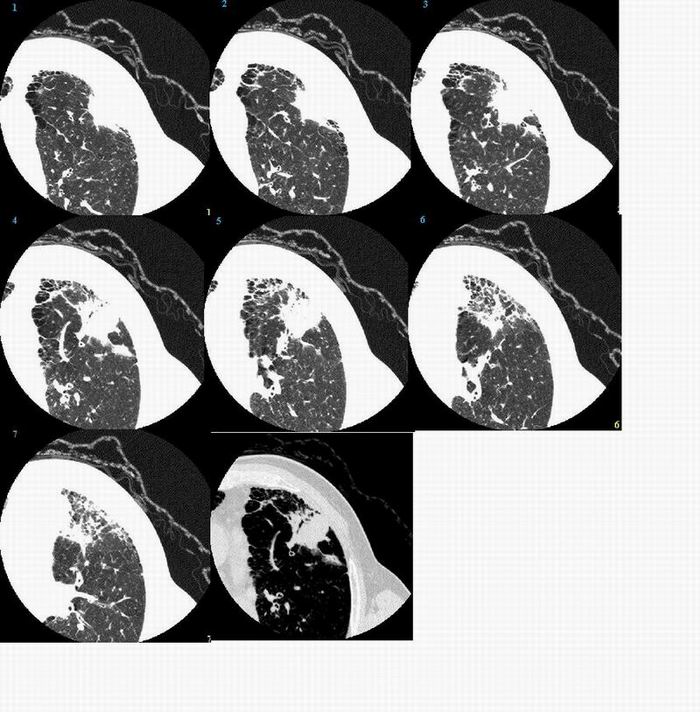

标题: 男,72岁,咳嗽,咯痰,进日痰中带血 [打印本页]

标题: 男,72岁,咳嗽,咯痰,进日痰中带血

不能排除周围型肺癌。

肺癌并淋巴管炎

考虑细支气管肺泡癌可能性大。

周围型肺癌,并阻塞性炎症

图像太局限,只能考虑左肺周围型肺癌。

不排除左肺周围型肺癌。

考虑炎症,不排除左肺周围型肺癌

考虑 左肺周围型肺癌

考虑细支气管肺泡癌

左肺周围型肺癌。

首先考虑炎性改变(结核),不除外周围性肺癌   肺间质增生部分纤维化  支气管扩张并感染

周围型肺癌可能

考虑:左肺周围型肺癌。

考虑左肺周围型肺癌。

考虑肺癌